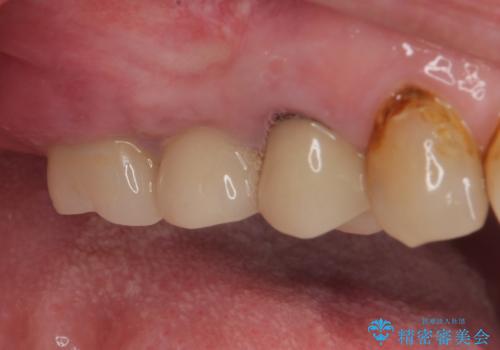

歯肉を開いて確認をしたところ、著しく骨欠損しており、目視でも歯根破折が確認されました。

3つある歯根の内、1つのみに骨欠損がある状態で、インプラント埋入に十分な骨の状態でした。

抜歯即時埋入・即時荷重の適応と判断されたため、インプラントによる補綴治療を行うこととしました。

埋入時に十分な安定値が獲得でき、埋入した際に仮歯を装着することができました。

術後の経過は安定しており、抜歯から3ヶ月で治療を終えることができました。